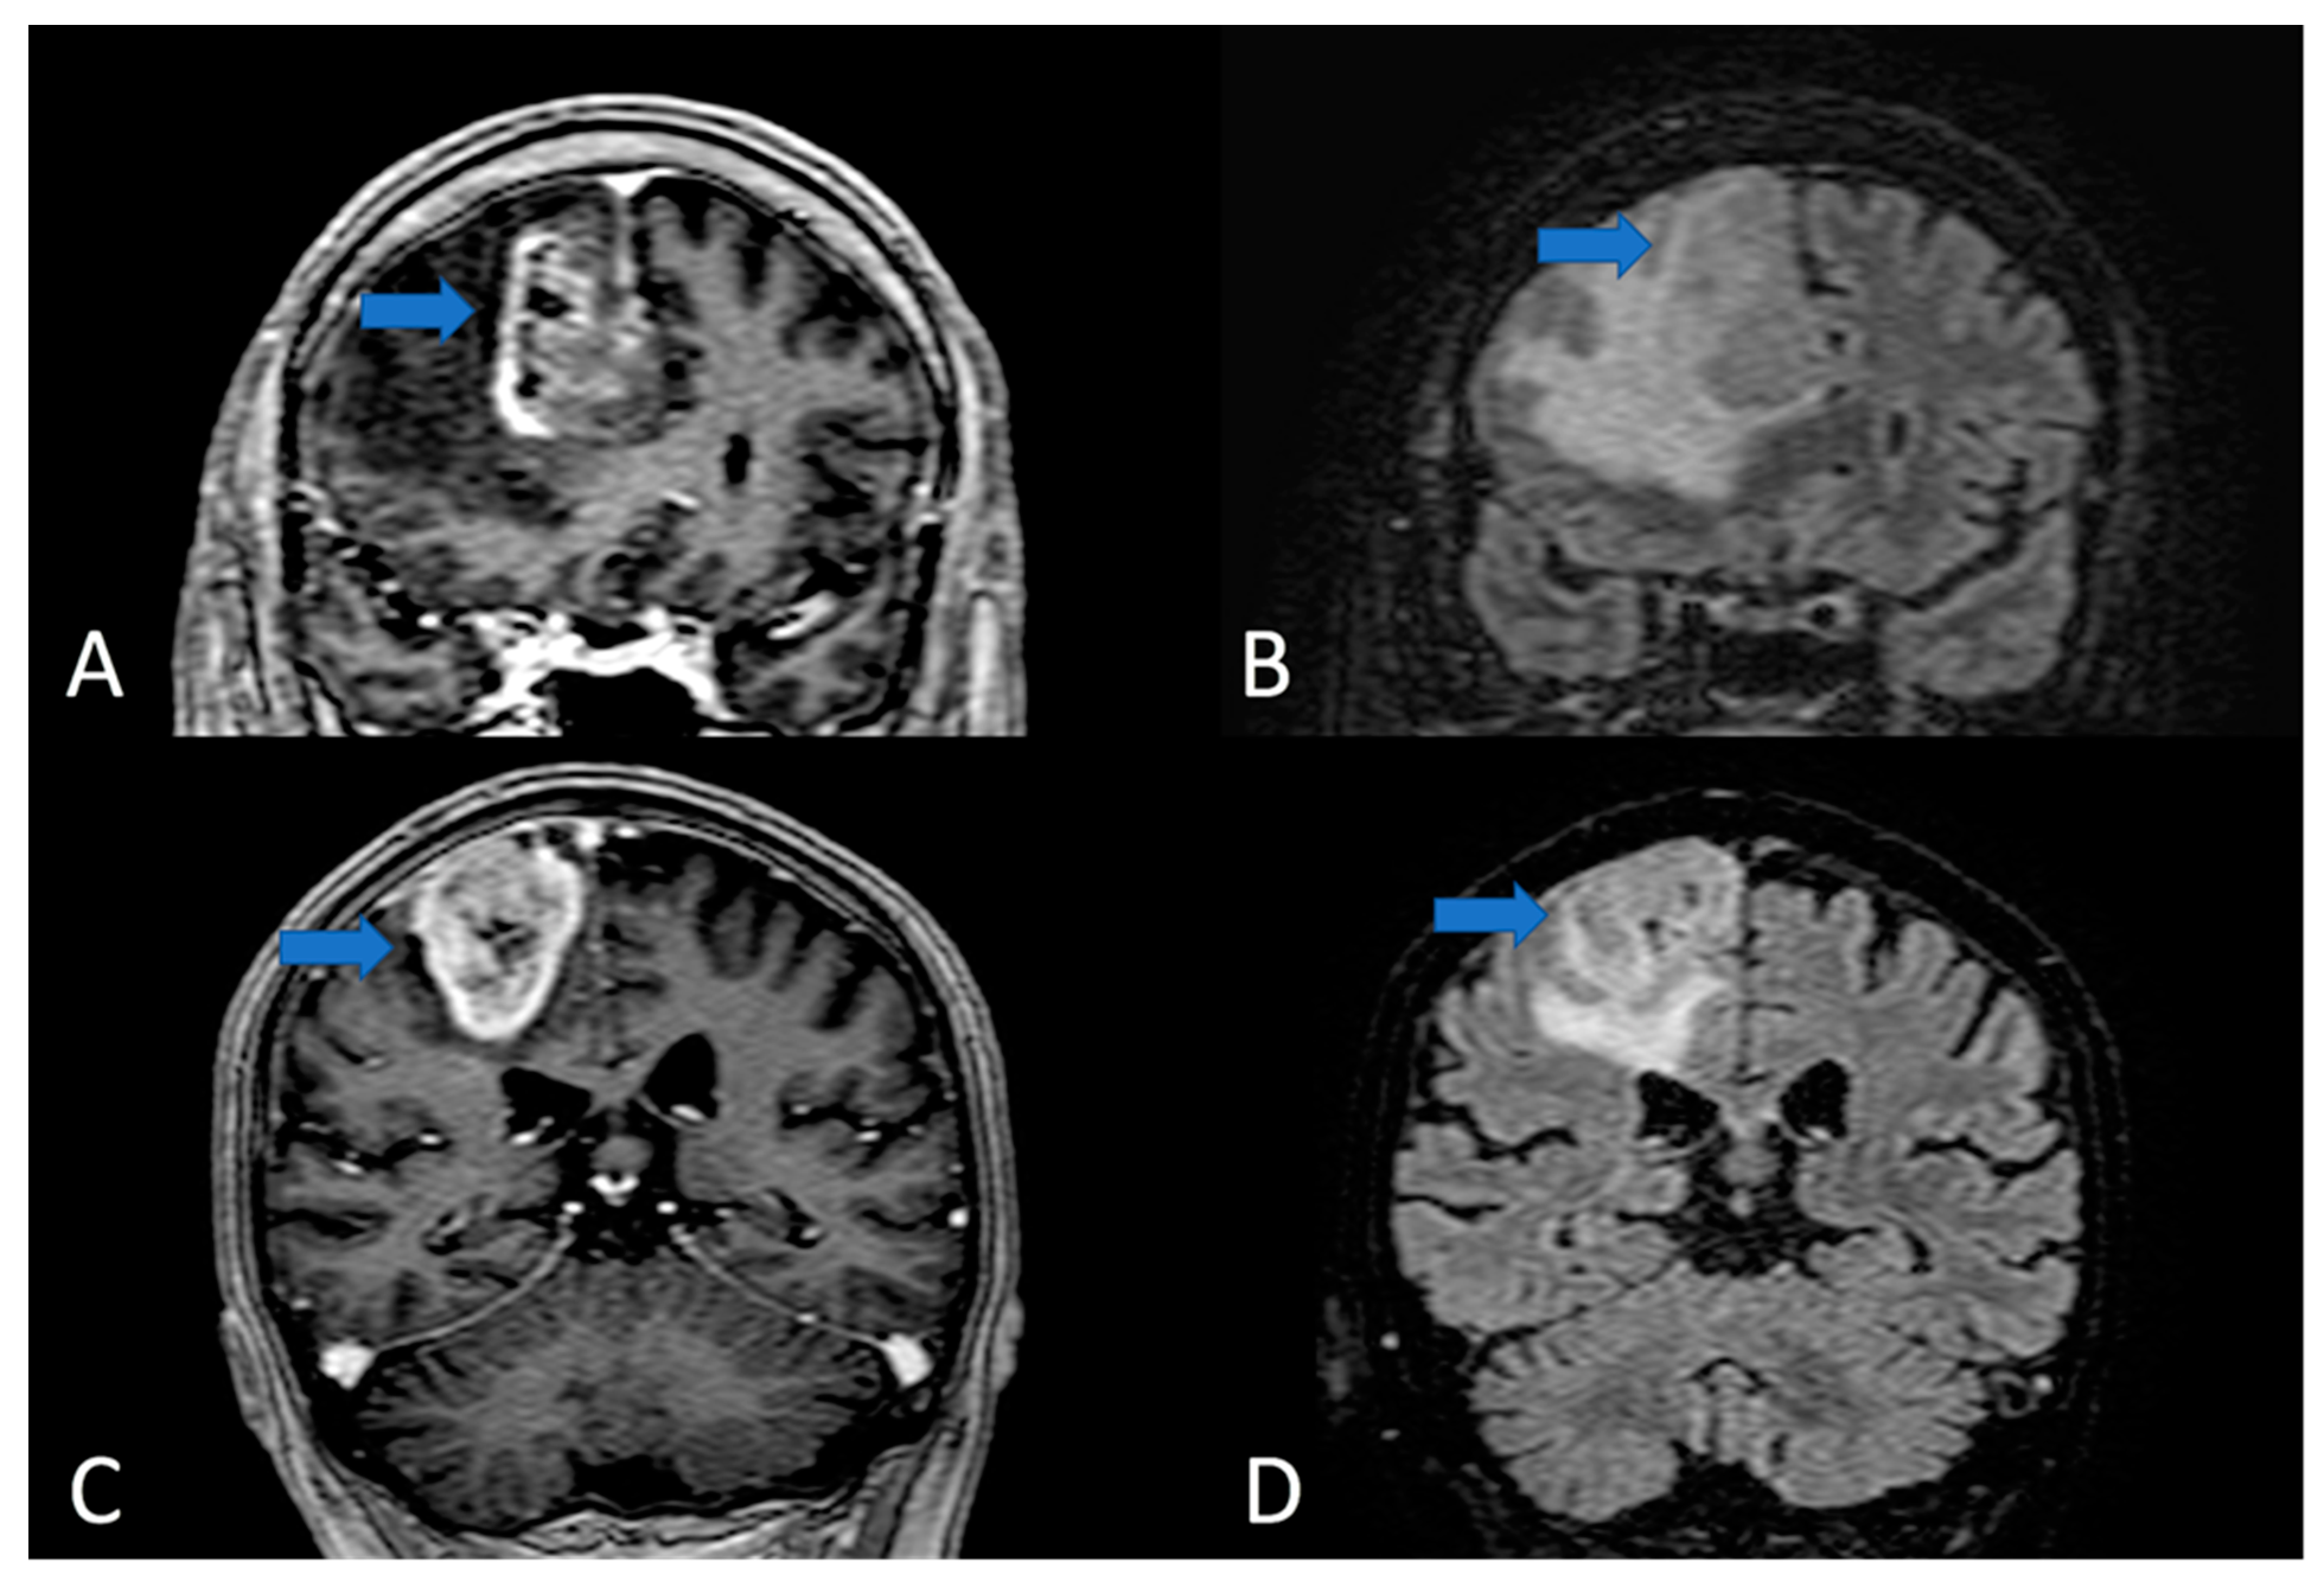

- Jiang, H.; Cui, Y.; Liu, X.; Ren, X.; Li, M.; Lin, S. Proliferation-dominant high-grade astrocytoma: Survival benefit associated with extensive resection of FLAIR abnormality region. J. Neurosurg. 2019, 132, 998–1005. [Google Scholar] [CrossRef]

- Al-Holou, W.N.; Hodges, T.R.; Everson, R.G.; Freeman, J.; Zhou, S.; Suki, D.; Rao, G.; Ferguson, S.D.; Heimberger, A.B.; McCutcheon, I.E.; et al. Perilesional Resection of Glioblastoma Is Independently Associated With Improved Outcomes. Neurosurgery 2020, 86, 112–121. [Google Scholar] [CrossRef]